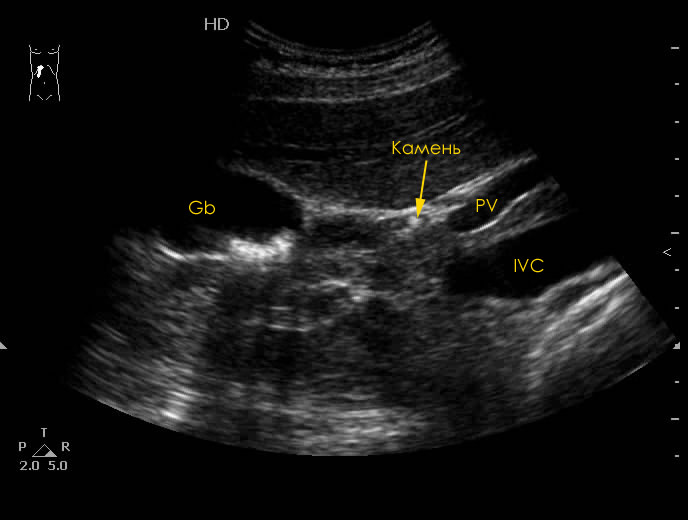

УЗИ ЖВП: конкремент в пузырном протоке

Воротная вена как раз и видна, точнее ее левая ветвь.